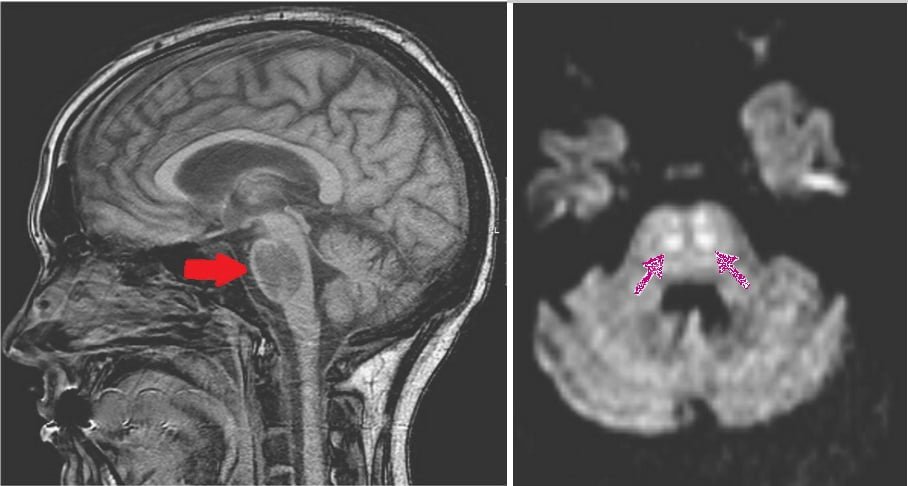

Hong Kong asıllı ABD'li aktör ve dövüş sanatları ustası Bruce Lee, 20 Temmuz 1973'te 32 yaşındayken hayatını kaybetmişti. O yıllarda yapılan otopsi sonucu Bruce'un beyin şişmesi nedeniyle hayatını kaybettiği ve buna Equagesic adlı ağrı kesiciyi kullanması gösteriliyordu. Şimdi ise yapılan yeni araştırmalar, Hollywood efsanesi Lee'nin hiponatremiden ölmüş olabileceğini ortaya koyarken, Klinik Böbrek Dergisi'nde uzmanlardan oluşan bir ekip, "Başka bir deyişle, böbreğin fazla suyu atamamasının Bruce Lee'yi öldürdüğünü düşünüyoruz" açıklamasında bulundu. 'BÖBREKLERİ FAZLA SUYU KALDIRAMADI' Priscila Villalvazo, Raul Fernandez-Prado ve Maria Dolores Sánchez Niño gibi böbrek hastalıkları uzmanlarının imza attığı araştırmada, beyin ödeminin sebebinin kandaki sodyum konsantrasyonunda azalma (hiponatremi) olabileceği yazıldı. Yani doktorlar, Lee'nin ölmeden önce esrar ve su içtiğini göz önüne aldığında tükettiği suyun böbrekleri için fazla gelmiş olabileceğini buldu. Bu durumun ise beyinde ödeme neden olduğu aktarıldı. Zira beyin ödemi, kandaki sodyum yoğunluğundaki azalmayla ilişkilendirildi. Lee'nin beyni öldüğünde bin 575 gram gelmişti. Normalde bin 400 gram olması gerekiyordu. 'SIVI BAZLI DİYET YAPMIŞTI' Lee'nin eşi Linda, Bruce'un ölümüne kadar sıvı bazlı bir havuç ve elma suyu diyeti yaptığını açıkladı. Bu açıklamanın da uzmanların teorisini destekler nitelikte olması dikkat çekti. Uzmanlar, araştırma sonucu, 'Bruce Lee'nin belirli bir böbrek fonksiyon bozukluğu biçiminden öldüğü' üzerinde durduklarını açıkladı. Bu sonuçlar, Lee'nin ölümünün 50 yıllık gizemi çözmüş gibi görünse de halen bazı kişiler onun Çinli gangsterler tarafından öldürüldüğünü hatta kıskanç bir sevgili tarafından zehirlendiğini savunuyor. Güneş ve sıcak çarpmasından öldüğü de teoriler arasında yer alıyor... [old_news_related_template title="'Power Rangers' yıldızı Jason David Frank hayatını kaybetti: İntihar şüphesi" desc="1990’lı yıllara damgasını vuran ünlü Power Rangers dizisinin yıldızı Jason David Frank 49 yaşında hayatını kaybetti." image="https://sozcuo01.sozcucdn.com/wp-content/uploads/2022/11/21/iecrop/1637953006762-adad-1_16_9_1669022472.jpg" link="https://www.sozcu.com.tr/hayatim/kultur-sanat-haberleri/power-rangers-yildizi-jason-david-frank-hayatini-kaybetti-intihar-suphesi/"]